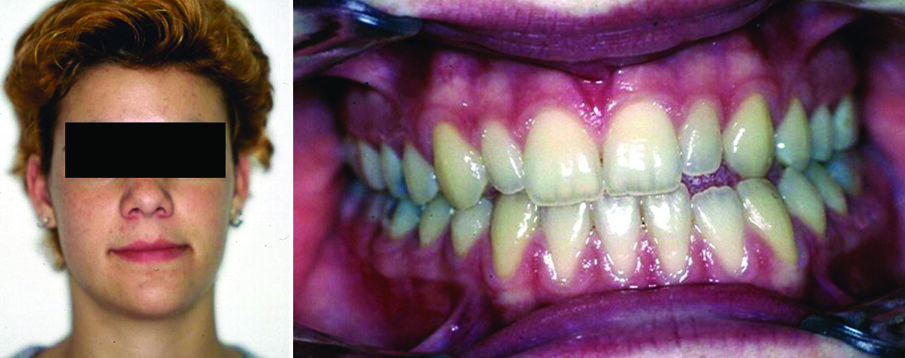

It is a chronic hypomobility and, if happens in growing subjects, it becomes a growth disorder (Figure 5). It results from intracapsular adhesions or ossification between the disc and temporal articular surface that attach the disc-condyle complex to the articular eminence. Its classification relates to the degree of limitation (partial or complete), location of the union (intracapsular vs. extracapsular), and type of tissues involved (fibrous, osseous, fibro-osseous). TMJ ankylosis occurs relatively infrequently. Principle causes include trauma, previous joint surgery, systemic or local infections, tumors, compressive function pattern and systemic diseases (6). Regarding history, patients report limited mouth opening without any pain, the condition has been present for a long time, and, if not associated with severe dentofacial deformity, patients do not feel that it poses a significant problem.

Figure 5. Facial photograph of a 16-year-old boy with osseous ankylosis of the left TMJ. The discrepancies include severe asymmetries in the mandibular body and ramus (a). Malocclusion is characterized by left anterior and posterior crossbite, tilting of the occlusal plane, and lower dental midline deviation to the affected side (b).